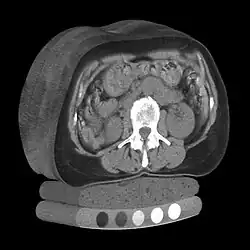

Image of cortical and trabecular bone of the spine by Quantitative computed tomography. Only the central trabecular portion is measured

Image of 3D volumetric QCT scan